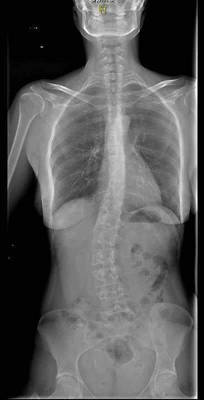

Todo iba bien hasta que al cumplir los 29 años empecé a trabajar en una empresa donde tenía que coger en alguna ocasión peso y hacer algo de esfuerzo. A raíz de aquello me empezó a doler bastante la espalda y el glúteo derecho. La vida me tenía guardada otro reto, fui al traumatólogo, me hicieron una radiografía entera de columna y…. ¡Sorpresa! Tenía una desviación de columna de unos 30 grados. La verdad es que nunca me había notado nada extraño ya que jamás me había dolido la espalda.

El cirujano me comenta que tengo una columna muy compleja ya que tengo escoliosis con bastante rotación vertebral, osteocondrosis por el desgaste de las vértebras en esa zona y espina bífida oculta. No estoy pasando buena época porque pensaba que la cirugía podría ser la solución de todos mis males pero claro la columna es una estructura muy compleja y no es fácil de aliviar sus dolencias.